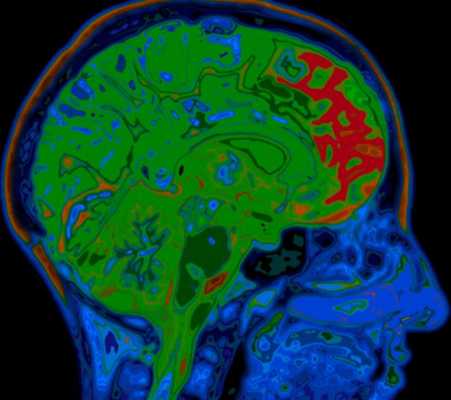

МРТ головного мозга. Аксиальная Т2-взвешенная МРТ. Цветовая обработка изображения. Опухоль мозга.

При дифференциальной диагностике опухолей головного мозга надо учитывать многие факторы включая эпидемиологические и диагностические. Золотым стандартом их выявления служит МРТ головного мозга. Многие центры МРТ СПб берутся за эту задачу, но мы рекомендуем Вам обследоваться именно у нас. При МРТ в СПб в дифференциальной диагностике опухолей в высоком поле и на открытом МРТ мы учитываем многие признаки, включая следующие: